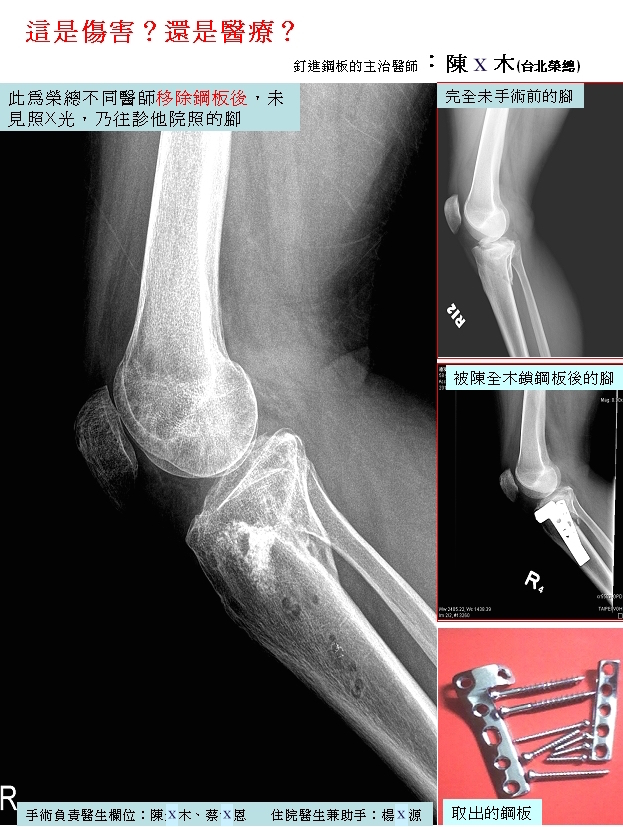

民眾提供之骨科糾紛案例01